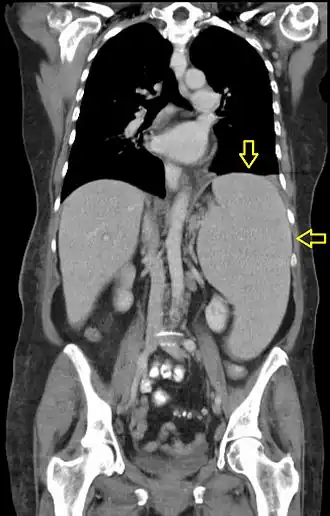

Гепатоспленомегалия (лат. Hepatosplenomegaly) — синдром, характеризующийся одновременным увеличением селезёнки и печени[1]. Диагностируется методами пальпации и перкуссии, а также при ультразвуковом или КТ-исследовании. Визуально при данном синдроме в области правого подреберья может наблюдаться выбухание, смещающееся при вдохе, обусловленное увеличенной печенью.